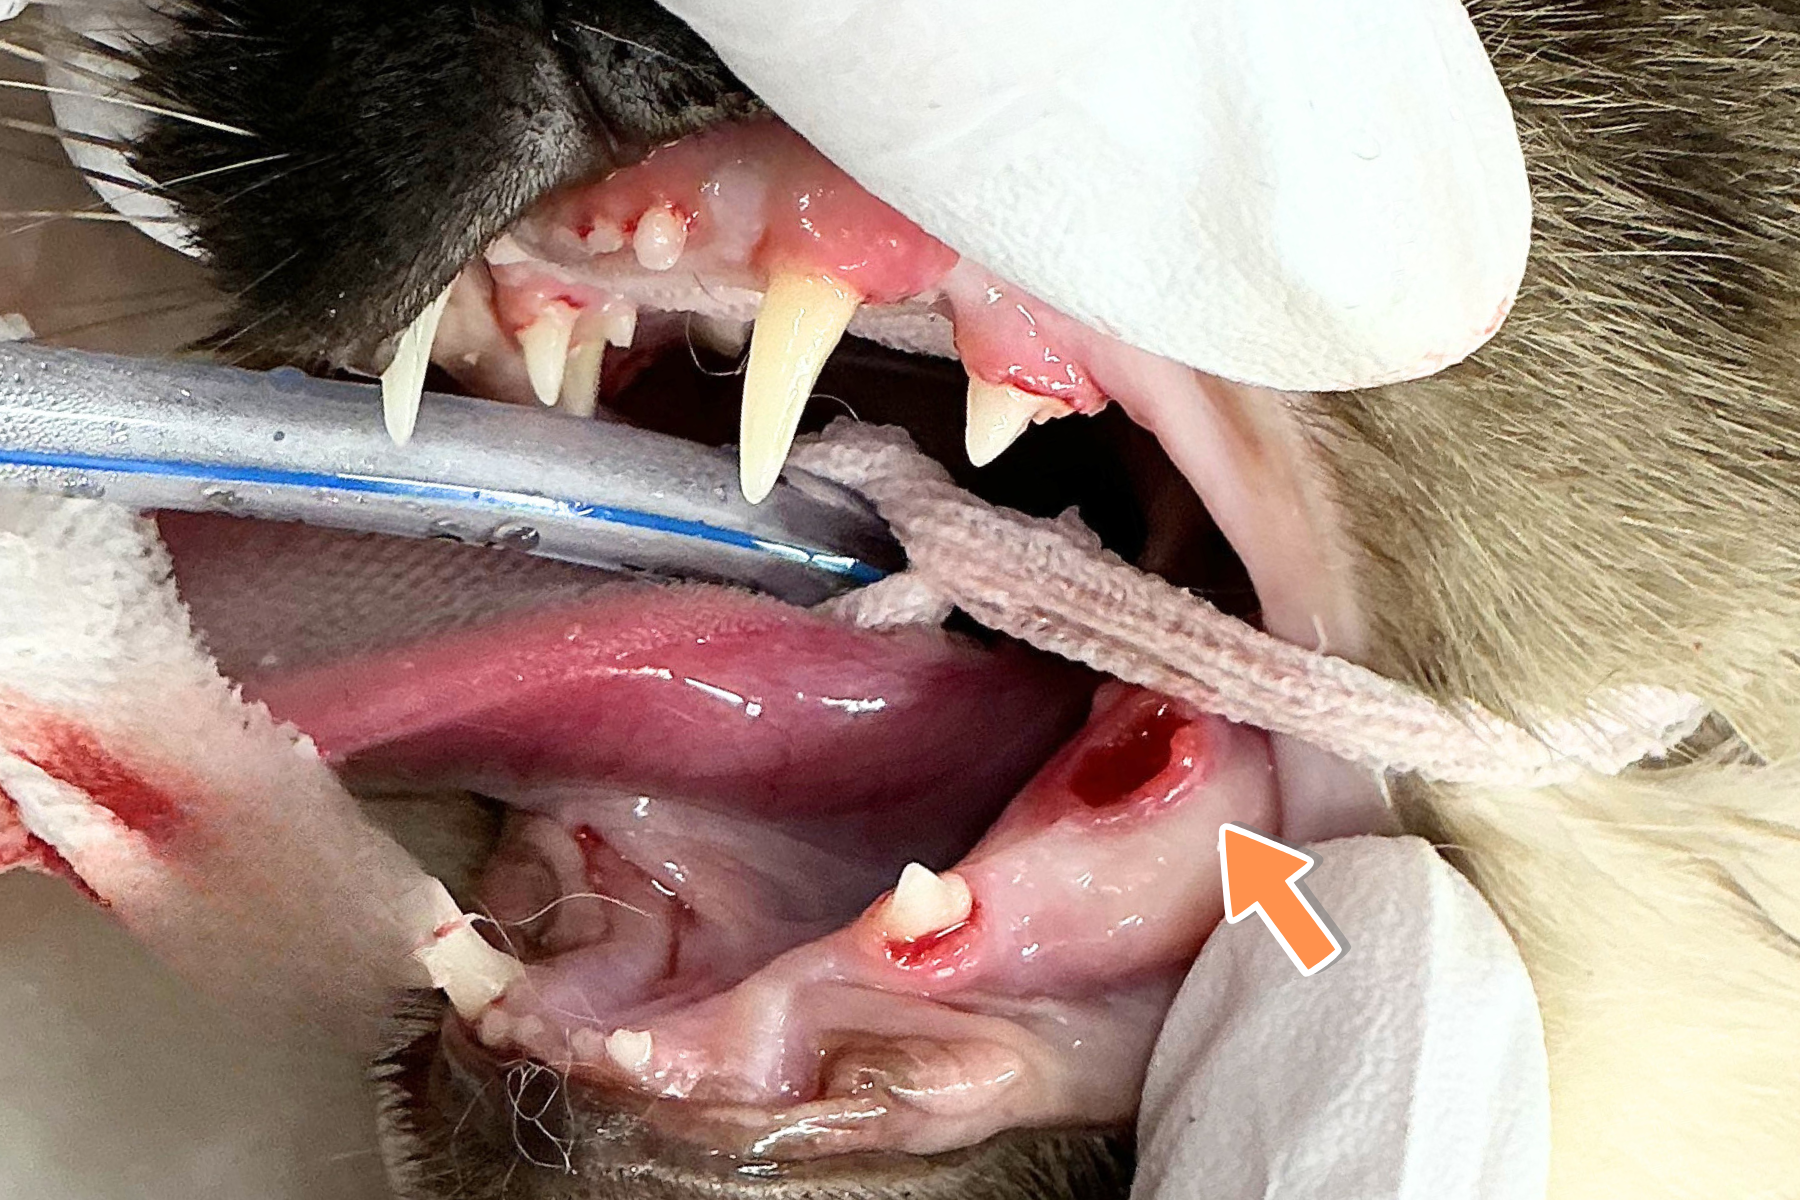

といった症状が見られており、左下顎の裂肉歯と呼ばれる大きな奥歯の部分にも動揺が認められたため、

歯周炎と判断し、麻酔下でのスケーリングと抜歯を計画しました。

裂肉歯は歯根が複数ある多根歯で、通常は分割抜歯が必要になることもあります。

今回の症例では炎症が強く、歯根があまり歯茎に付着していなかったため、分割抜歯を実施することなく比較的容易に抜歯することができました。

抜歯後、歯肉に生じた穴が大きかったため、2糸縫合を実施しました。